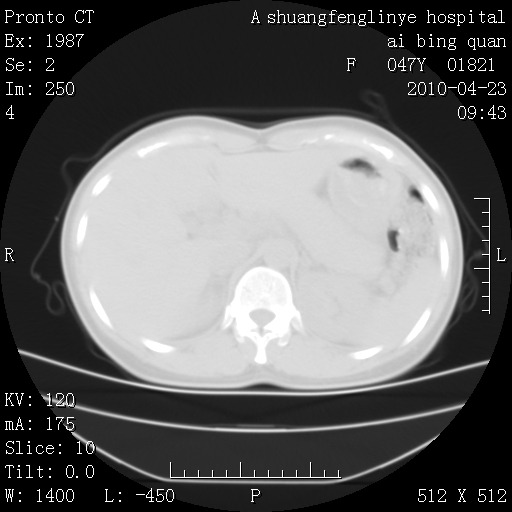

标题: CT25944:胸痛、气短、前几日高烧!肺Ca?请会诊!

双肺多发结节,考虑转移瘤,肺癌肺转移不除外

双肺多发结节,部分密度较高,最大结节边缘光滑。临床有“胸痛、气短、前几日高烧”病史。首选考虑:右肺感染性病变!建议积极消炎后复查!